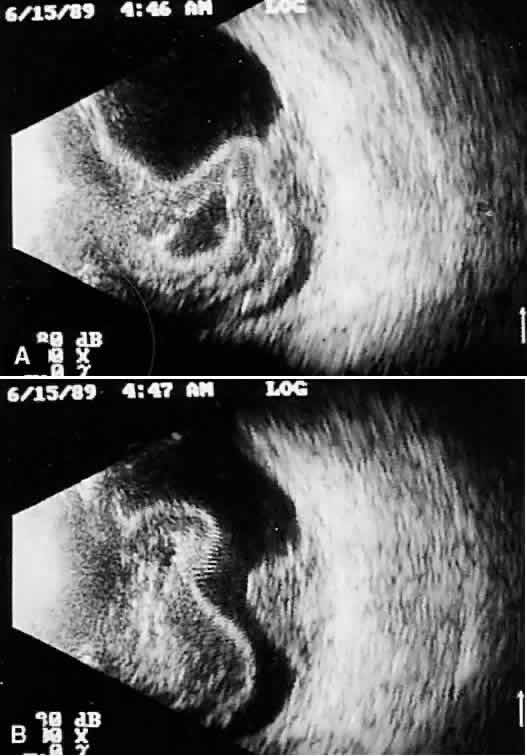

Fig. 14. Contact B-scan: choroidal hemorrhage/vitreous hemorrhage secondary to blunt trauma.

Fig. 15. Contact B-scan: large choroids (anteroposterior view) and portion of scleral implant (at bottom of display screen).